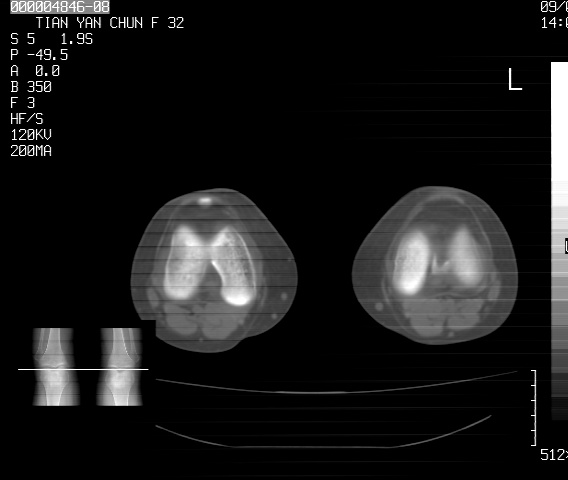

标题: CT18487:请会诊,女32岁,左膝疼痛数日 [打印本页]

标题: CT18487:请会诊,女32岁,左膝疼痛数日

关节面软骨有硬化环考虑退行性变

定位片可见髁间棘骨质增生,支持膝关节退行性变。

定位片可见髁间棘骨质增生,支持膝关节退行性变。建议mri 检查

考虑骨性关节炎